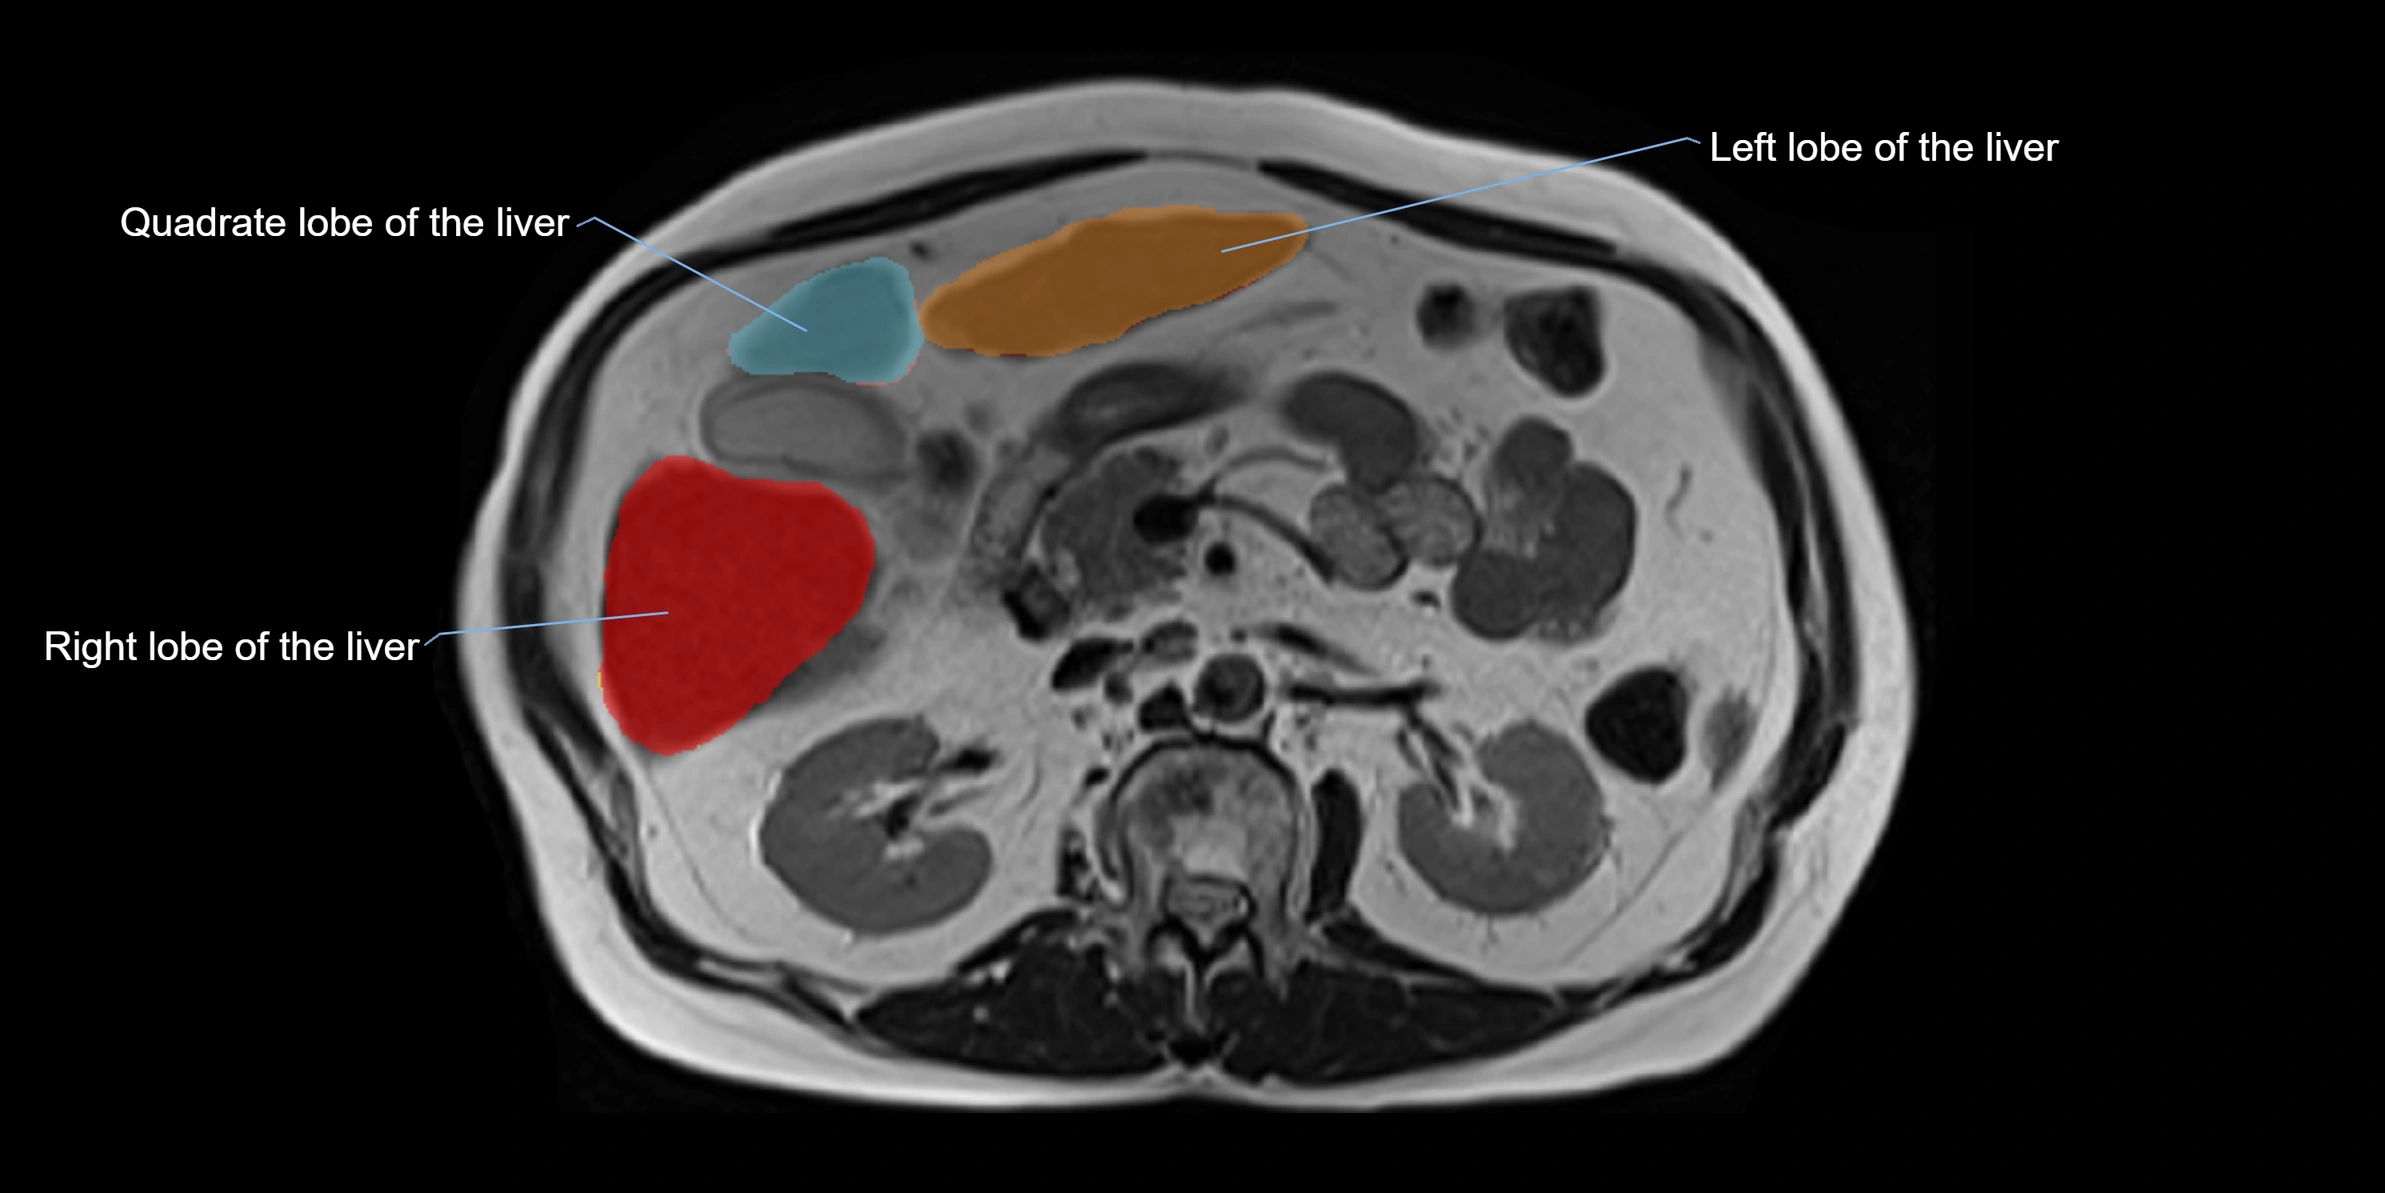

The caudate lobe of the liver is a distinct anatomical subdivision of the liver, designated as segment I in Couinaud’s classification. It lies on the posterior surface of the liver, between the fissure for the ligamentum venosum (left boundary) and the groove for the inferior vena cava (IVC) (right boundary). Superiorly, it is related to the posterior liver surface, and inferiorly it is separated from the left lobe by the porta hepatis.